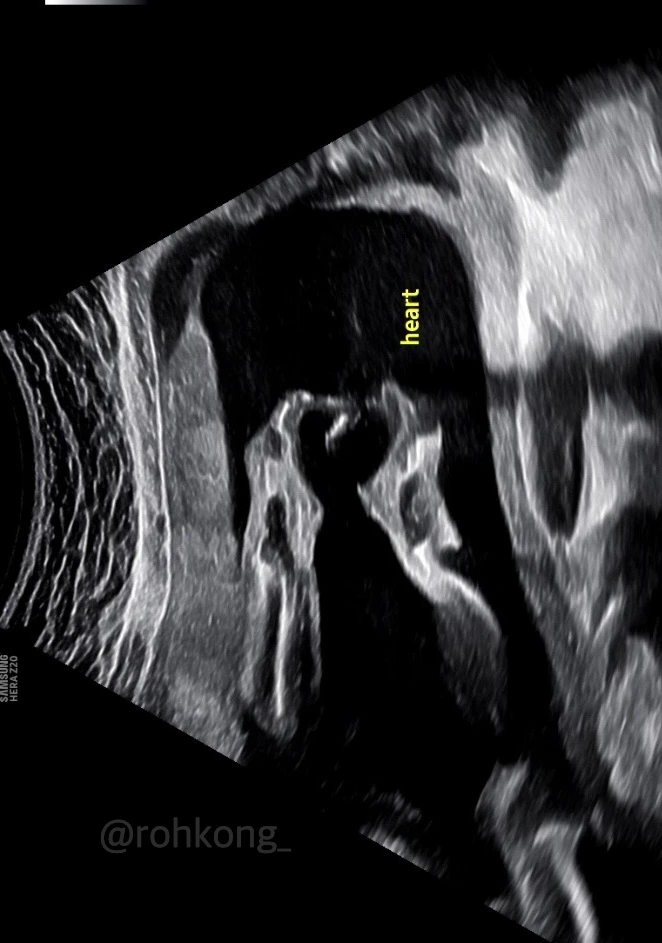

약을 마시고 태동이 요란한 토롱이(태명) 초음파를 보았다. 얼굴을 보는 것은 생각보다 힘든 일인데, 발이 너무 발 같아서 이상했다. 사람발이 다 되었다. 귀엽고 신기했다. 발가락 5개, 5개, 손가락 5개, 5개, 이런저런 뼈, 머리, 심장, 신장, 간..

여러 신체기관을 간호사 선생님께서 확인해 주셨다.

사람이 다 되었다.

발이 너무 발 같다

다시 초음파실로 가서 토롱이 얼굴을 보러 갔다.

노력 끝에 아주 조금 얼굴을 봤다. 그냥 이렇게 과학기술이 발전해서 얼굴이고 손이고 발이고 볼 수 있는 게

너무 신기하고 귀엽다. 친오빠한테 사진을 보여주니 한참이나 “뭐라 말해야 할지 모르겠다”

라고 하더니 "신비롭다"라고 했다.

맞아 신비롭다.

손으로 하트를 만들었다